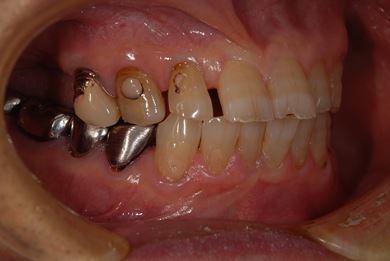

抜歯即日スピードインプラント治療+歯周外科治療

| 性別/年齢 | 男性 / 62歳 | ||||||||||||||||||||||||||||||||

| 主訴 | 左下の奥歯のブリッジがゆれて、痛みがある。 | ||||||||||||||||||||||||||||||||

| 治療方針 | 抜歯と同時にインプラント埋入を行い、治療期間を短縮する。 | ||||||||||||||||||||||||||||||||

| 治療内容 | インプラント2本(抜歯即日スピードインプラント)、ハイブリッドセラミッククラウン2本、歯周外科治療 | ||||||||||||||||||||||||||||||||